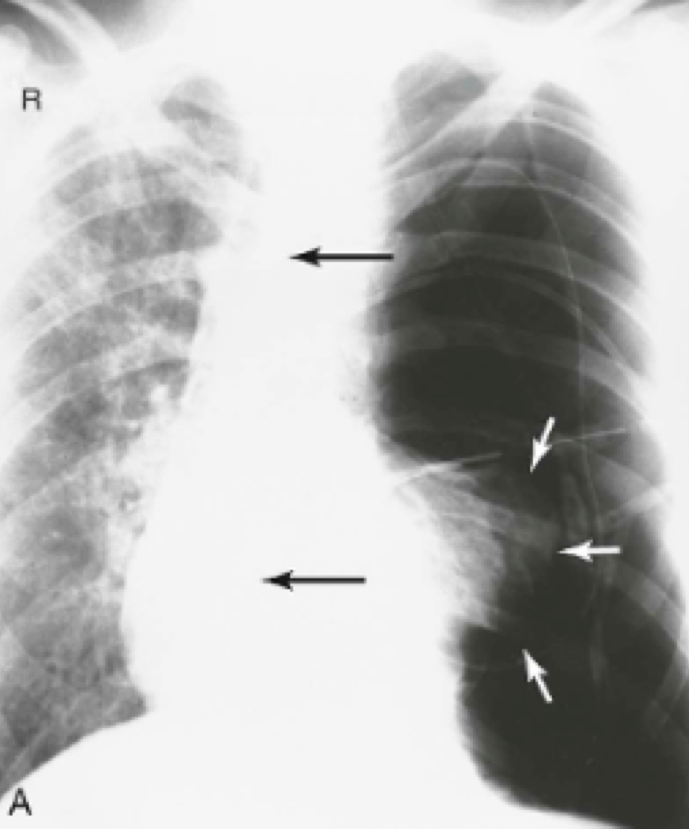

Question 19

Question

What is in this image?

Answer

• Pancoast Tumor

• Fungal Ball

• Hair braids

• bulla